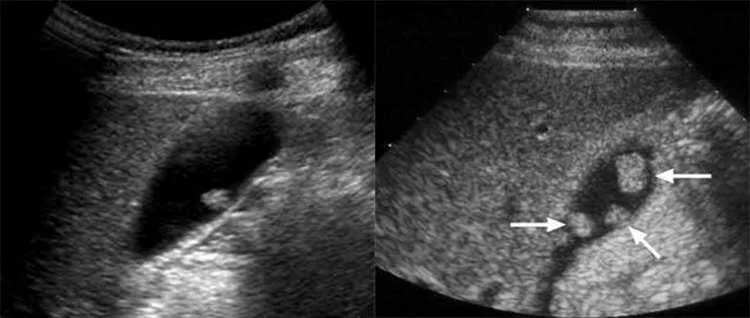

Полип в желчном симптомы лечение